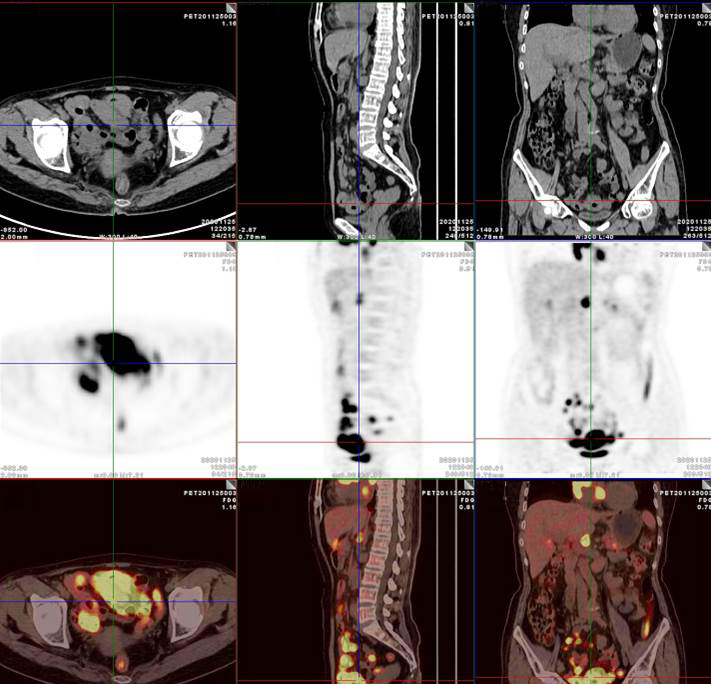

PET/CT影像圖

腸系膜多發(fā)淋巴結(jié)放射性攝取增高

多段小腸腸管放射性攝取增高

影像診斷

考慮淋巴瘤,請結(jié)合臨床病理